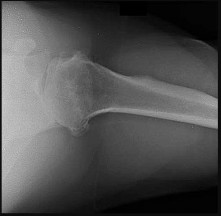

Figures 32a through 32c are the radiograph and CT scans of a 75-year-old smoker with hypertension who sustained a ground-level fall without loss of consciousness with impact to her

The radiographs and CT scans indicate a 4-part left proximal humerus fracture with tuberosity comminution. Based upon her preinjury level of activity and current imaging studies, nonsurgical management is not the correct option to restore her ability to perform activities of daily living, including hygiene care. There has been enthusiasm among surgeons regarding the use of the reverse shoulder prosthesis as the primary mode of surgical treatment of certain 3- and 4-part proximal humerus fractures. The main attribute of this implant is its ability to achieve functional shoulder forward flexion and abduction regardless of tuberosity healing, position, and degree of comminution. Nevertheless, repair and union of the greater tuberosity fragment during rTSA demonstrate improved external rotation, clinical outcomes, and patient satisfaction than outcomes achieved after tuberosity resection, nonunion, or resorption. Based upon this patient’s age and imaging findings, an rTSA would provide pain relief and improved function with complication rates similar to those associated with hemiarthroplasty. Open reduction with internal fixation would not be a viable option because of the high probability for a dysvascular head, increased risk for nonunion, and potential for revision surgery, including arthroplasty. Hemiarthroplasty for 4-part proximal humerus fractures remains a viable option for patients younger than 70 years of age with minimal tuberosity comminution and an intact rotator cuff who can comply with a postsurgical rehabilitation program. Most studies indicate significant pain relief with this modality with significant variation in functional outcomes. In this clinical scenario, the patient’s injury may not be best served with hemiarthroplasty because of uncertainty regarding functional outcome.